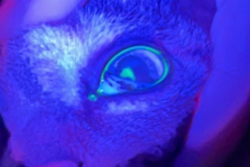

Before:潰瘍部分に染色液がのりブルーライトを当てると光ります

After:点眼開始1週間後、染色範囲が狭まりました

目が開きづらそう、目を気にしている、瞬膜が出ている

フルオレセイン角膜染色を実施し角膜潰瘍あり、結膜細胞診で核内封入体を認めヘルペスウイルス感染症の関与も示唆されました。角膜障害治療薬の点眼薬と抗ヘルペスウイルス薬の内服で治療を開始し、徐々に角膜潰瘍の治癒を認めました。ストレスが発症に関与するので出来る限り負担のないように注意しました。

角膜潰瘍は角膜に傷がつき痛みを伴う疾患です。原因としては外傷、異物、逆さまつげ、ドライアイ、免疫異常、感染(ウイルス、細菌、真菌)などがあります。角膜潰瘍は悪化してしまうと角膜穿孔(目に穴があいてしまう)になることもありますので早期の治療が大切です。特に猫ちゃんではヘルペスウイルスの関与が多いため出来る限りストレスのないような治療をご相談しながら選択できればと思います。点眼薬や軟膏、内服薬など様々な方法をご提供させていただきます。